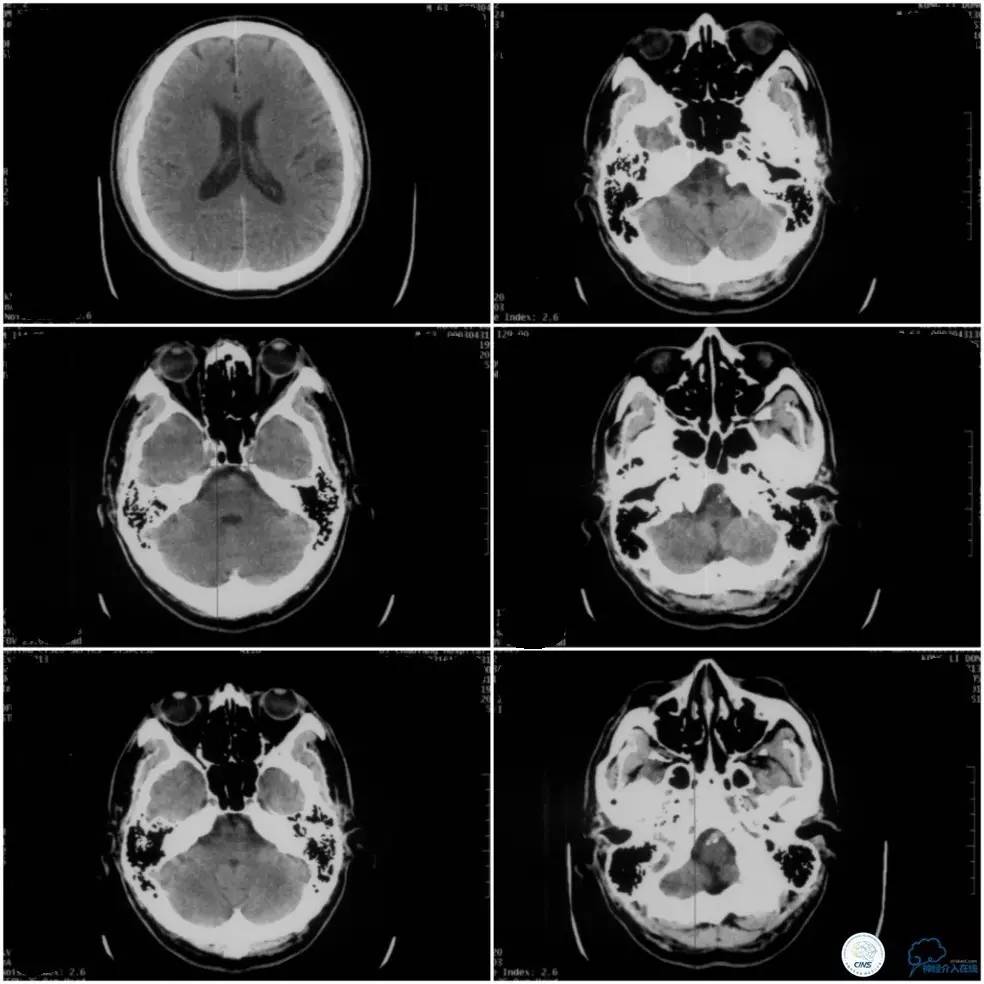

1月前无明显诱因出现后枕部头痛,伴双眼疼痛,以右眼为著,呈胀痛,无视物不清,无肢体活动及意识障碍,后就诊邻近医院眼科查眼底,未能明确诊断,给予对症治疗,症状缓解不明显。至邻近医院就诊查头颅CT示陈旧性脑梗塞,椎基底动脉走行区见钙化病变(图1)。

图1